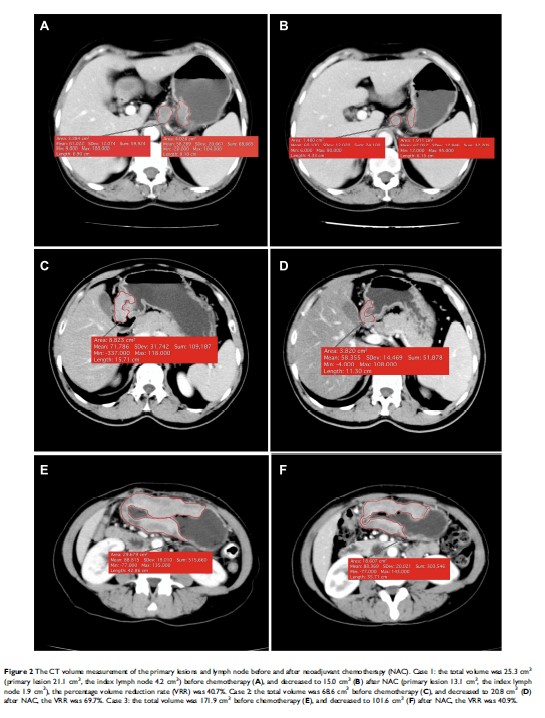

计算机断层扫描容量法与新辅助化学疗法治疗的晚期胃癌预后的相关性